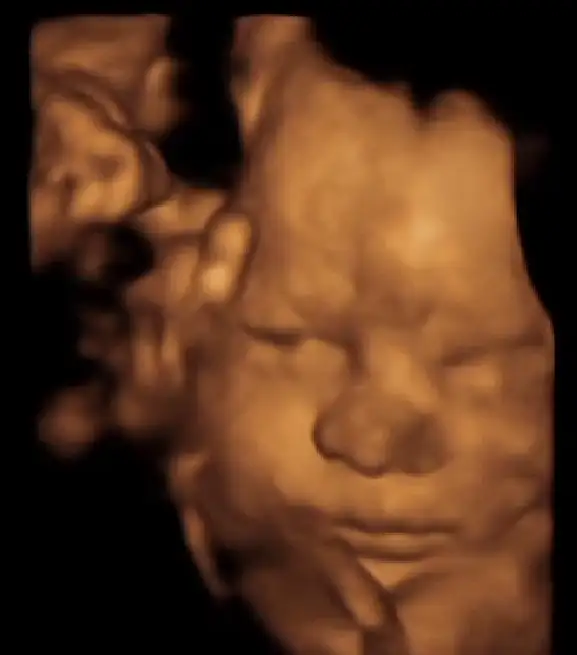

Ben her kontrole eşimle gidiyorum normalde , ama dünki mecburi hafta içi olunca eşim izin alıp gelemedi , ben tek gittim . Eşimle gittiğim her kontrolde iki elini, hatta ayaklarını bile yüzüne kapayan kızım , dün bana şov yaptı resmen . 2-3 tane güzel poz alınca pat diye sırtını döndü direkt , bu sana yeter dedi zaar